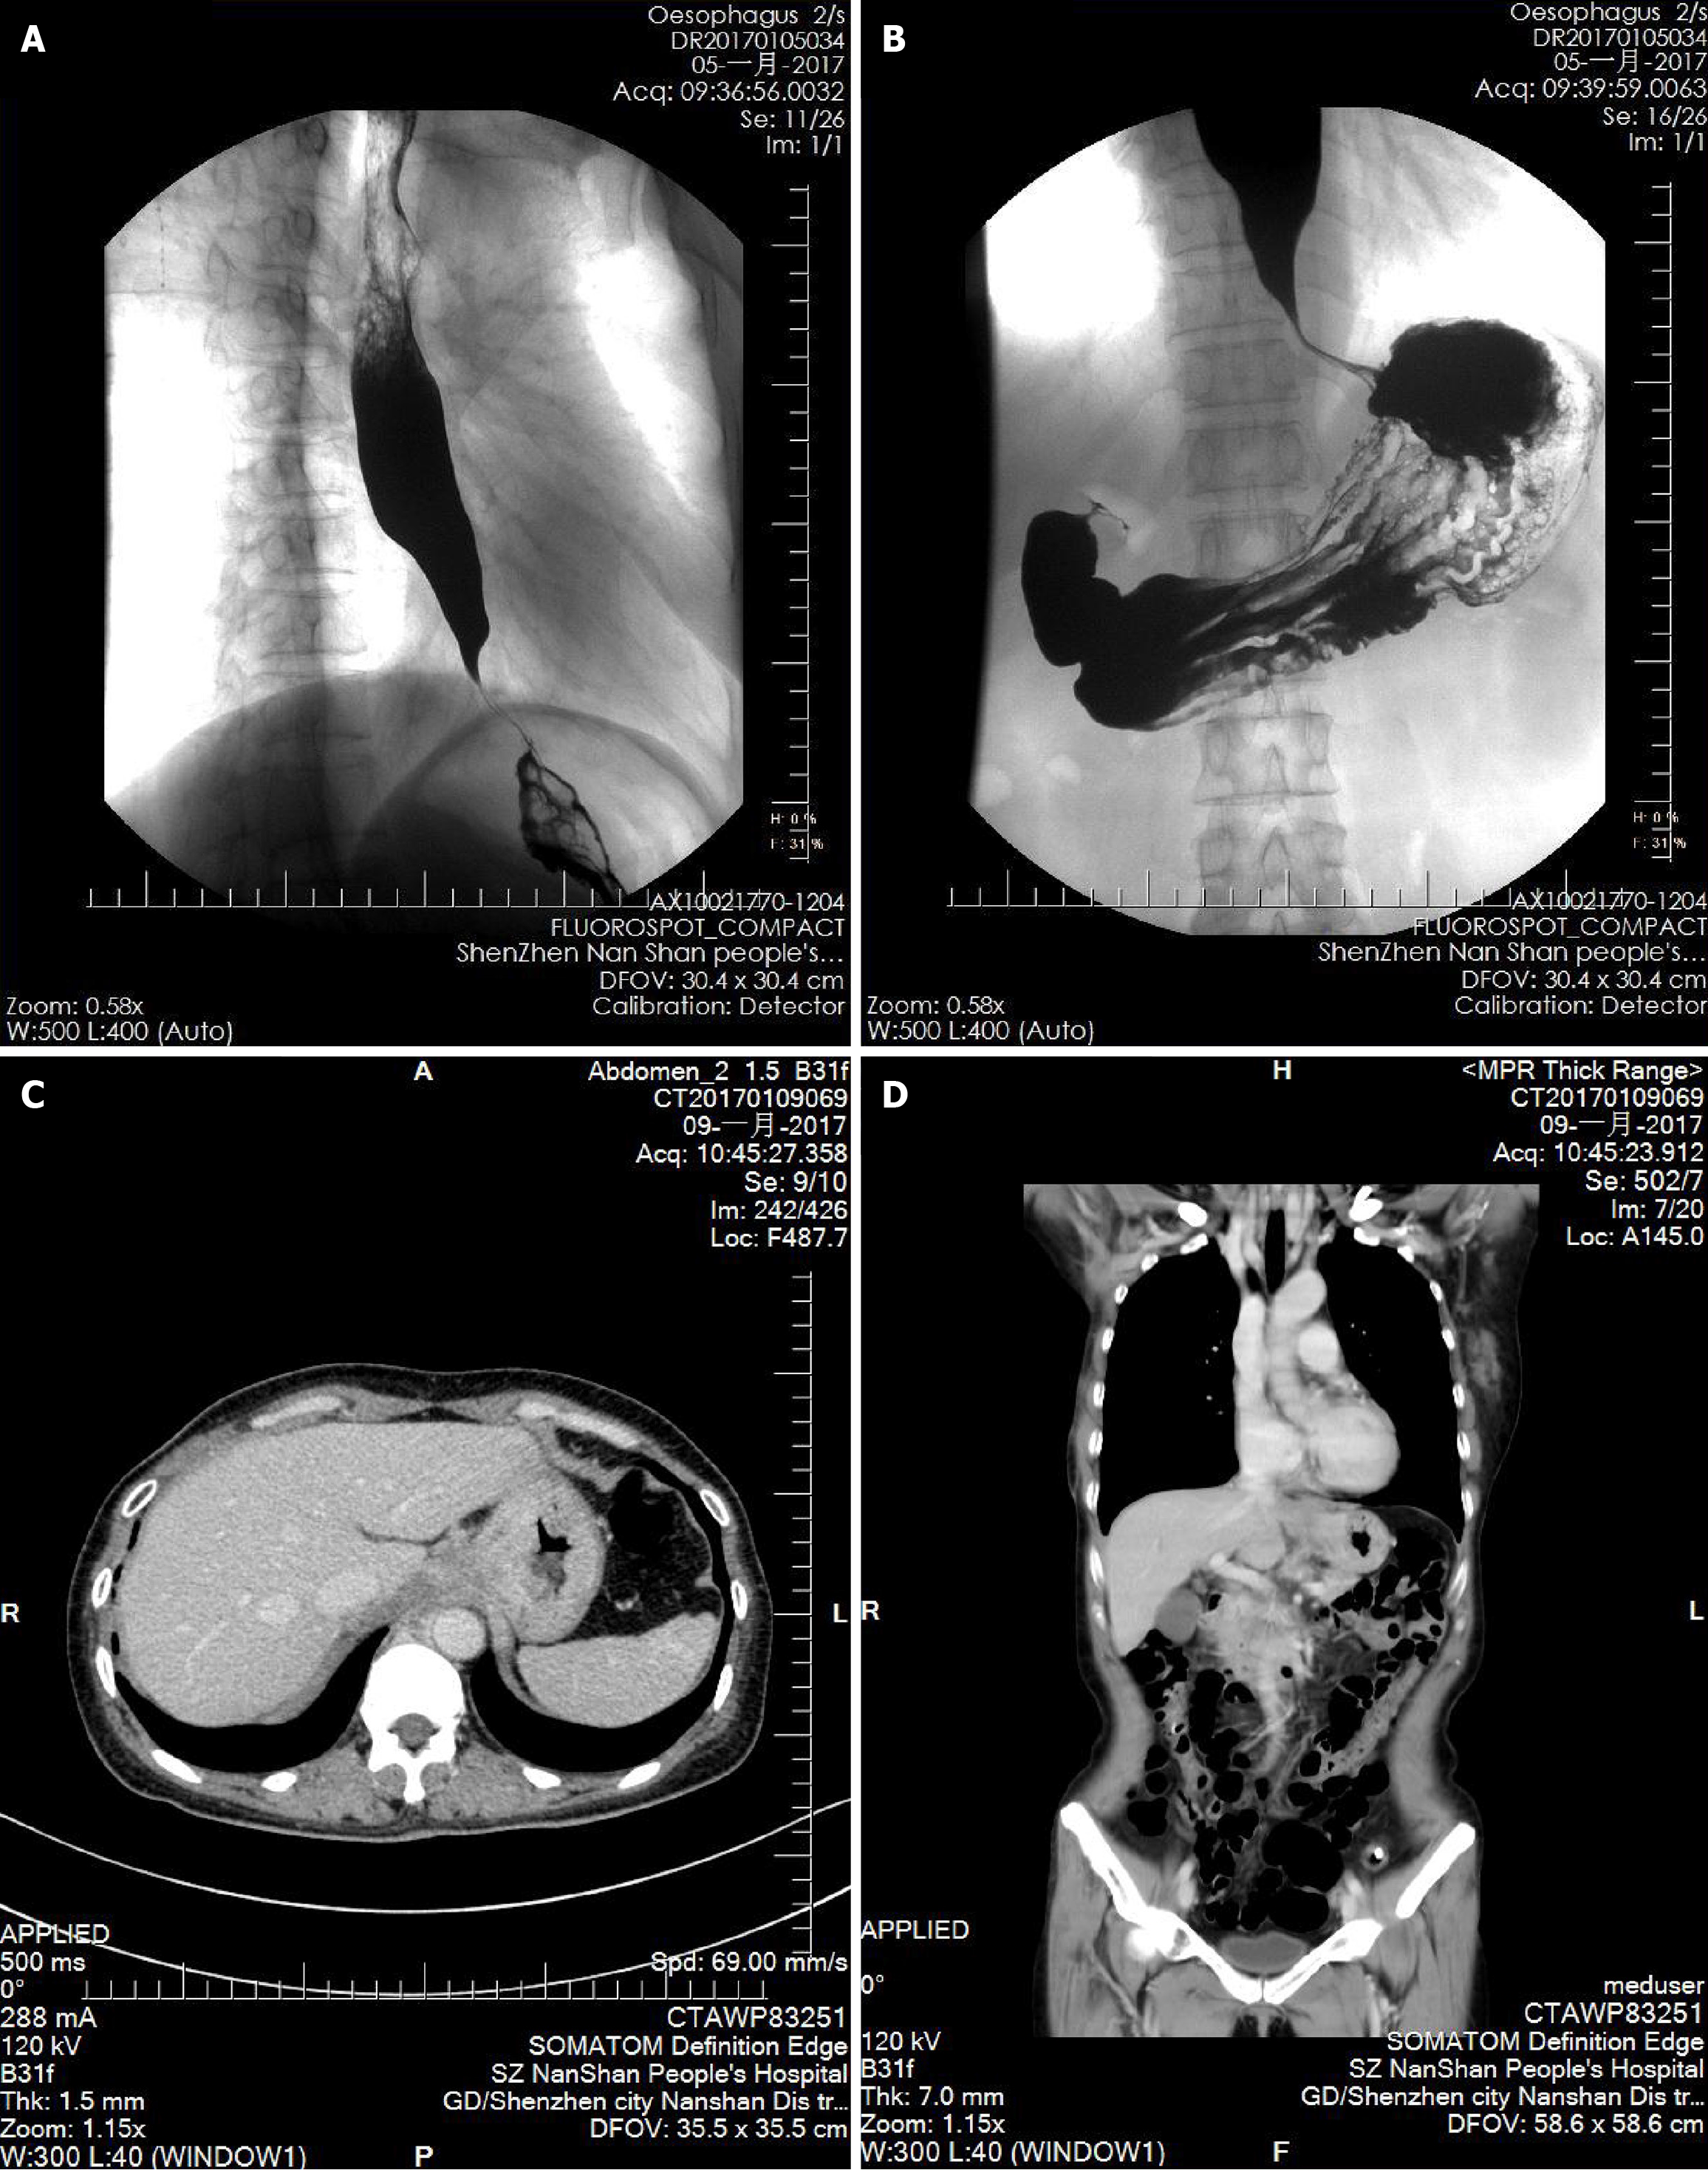

Figure 3 Thoracoabdominal computed tomography imaging.

A and B: In January 2017, the barium meal revealed the classic “beak sign"; C and D: In January 2017, computed tomography showed space-occupying lesions at the cardia and the fundus of the stomach, with metastatic lymph nodes in the surrounding retroperitoneal area.